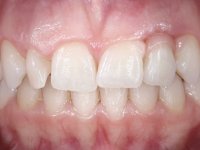

Female patient, 24 years of age, non-smoker. The clinical situation resulted from an orthodontic treatment performed with the intention of resolving a problem of unilateral agenesis of the left lateral incisor. After orthodontic correction, an implant was placed at the site of tooth 2.2. During the period of osseointegration the patient used a removable orthodontic appliance with a prosthetic tooth. Upon assessment of the situation, I registered the following aesthetic conditions:

1. The cervical level of the teeth 1.3.1.2 and 1.1 are at a more incisal level than the teeth 2.1 and 2.3.

2. The distal papillae of 2.1 and mesial of 2.3 disappeared.

3. Slight radicular exposure in distal 2.1 and mesial 2.3.

4. The edentulous space corresponding to the high and narrow 2.2.

5. Tooth 1.2 with microdontia and rolled.